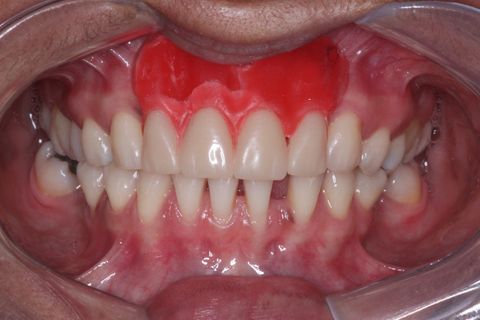

Provisórios instalados . Foto com um ano e meio após a instalação do enxerto e dos implantes. Paciente não compareceu antes para a finalização do trabalho devido problemas particulares

Minipilares instalados. Nota-se apenas 3 minipilares pois um dos implantes foi perdido. Instalamos um novo implante que também foi perdido. Optamos em manter apenas 3 implantes e finalizar a prótese fixa parafusada.